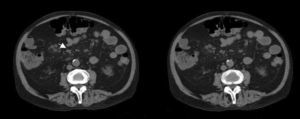

Caso 2Varón de 63 años con antecedentes de hipertensión arterial sistémica, insuficiencia renal, artritis y lumbalgia de 9 años de evolución, con diagnóstico de espondiloartritis. Presentó uveítis posterior y vitritis de ojo derecho, y 3 episodios de pancreatitis con ingreso en el servicio de Digestivo, en el que se realizó TC que evidenció adenopatías mesentéricas inespecíficas (fig. 1) y gastroscopia con bulboduodenitis erosiva con toma de biopsia. Un mes después ingresó de nuevo en el servicio de Digestivo por fiebre, diarrea y dolor abdominal. Se recibió el resultado de la biopsia duodenal (fig. 2) que se realizó en ingreso previo, con diagnóstico de enfermedad de Whipple. Se instauró tratamiento con ceftriaxona, imipenem, y posteriormente trimetoprima/sulfametoxazol, durante 2 años, añadiendo cefixima los 2 primeros meses.